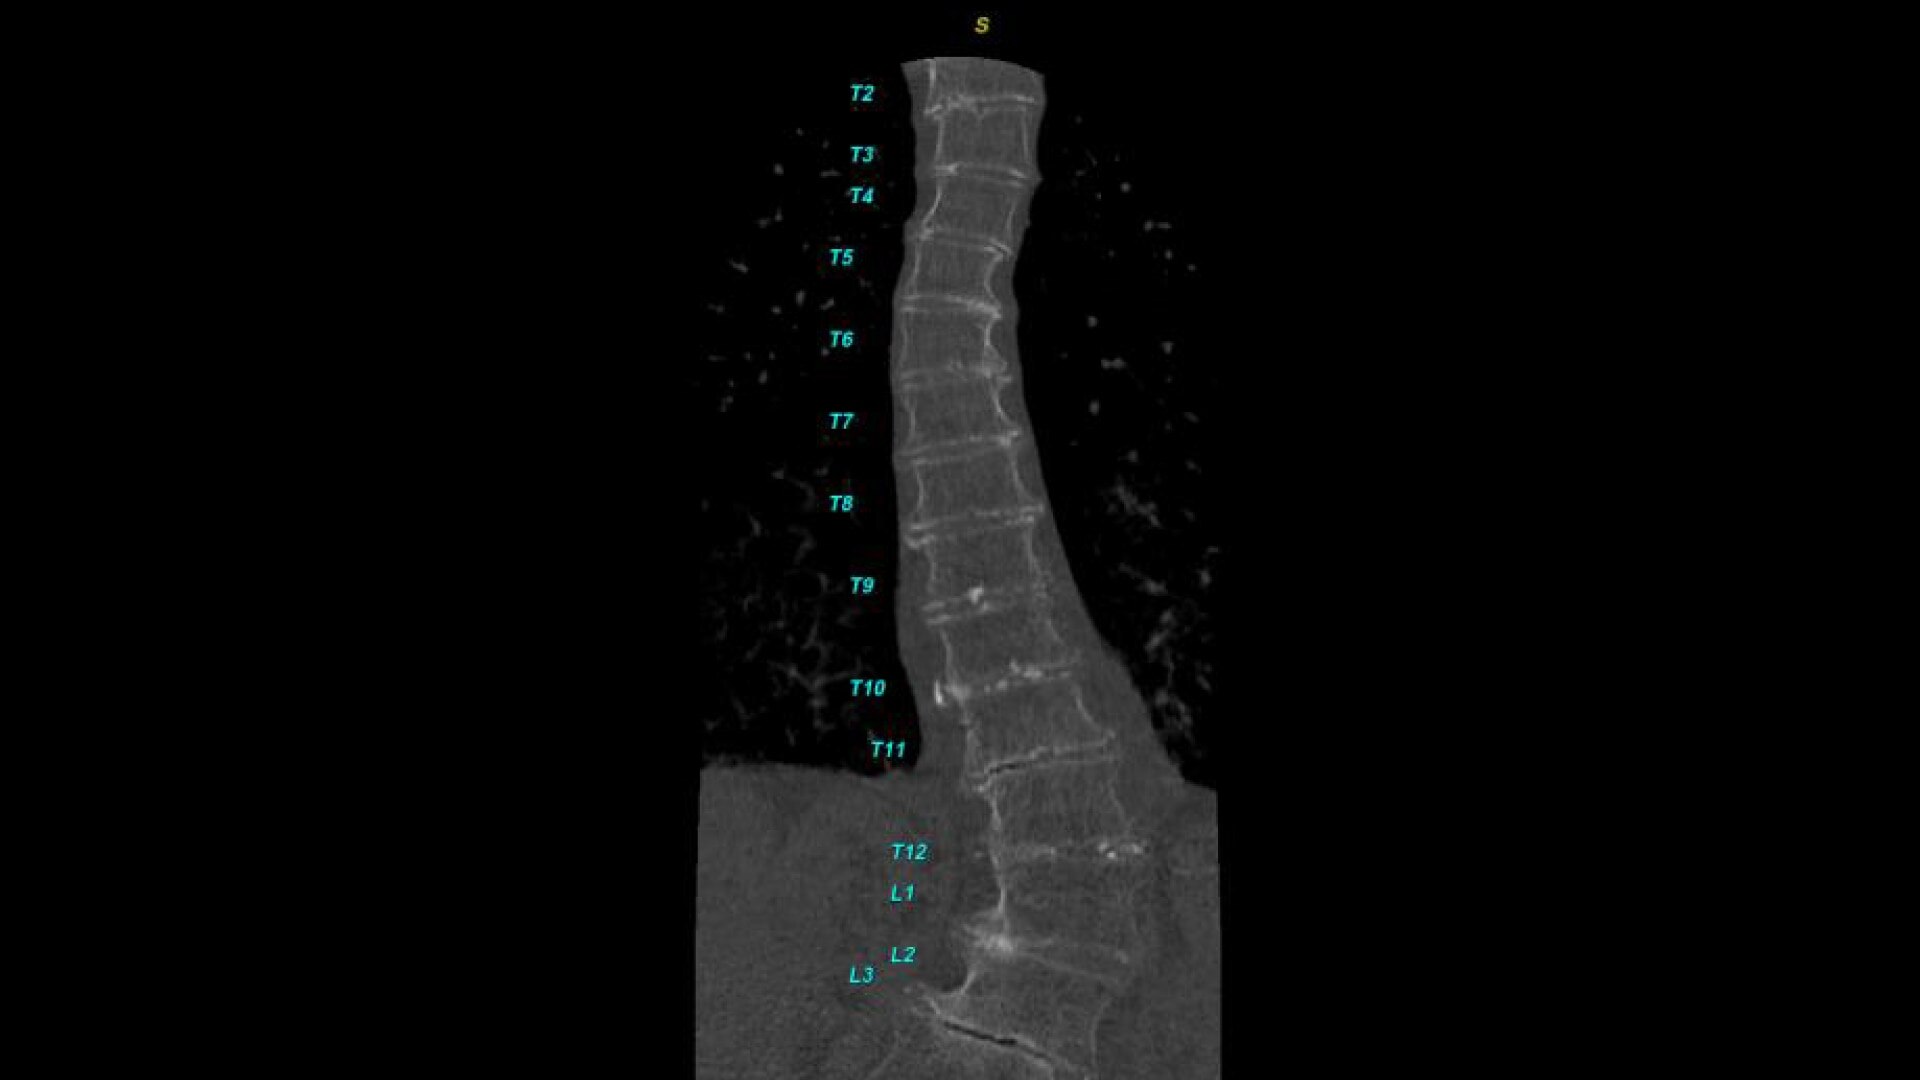

Bone VCAR

Spine assessment with deep-learning based CT application.

Automated spine identification and labelling.

>90% labeling accuracy based on Deep learning algorithm trained on global datasets acquired with a broad range of acquisition parameters.

• Automated spine labeling

• Automated generation of a 3D trace to generate oblique and straightened reformat views

• Automated generation of oblique views perpendicular to vertebral bodies and disc spaces

• Works on full spine acquisitions as well as limited acquisitions containing segments of the spine